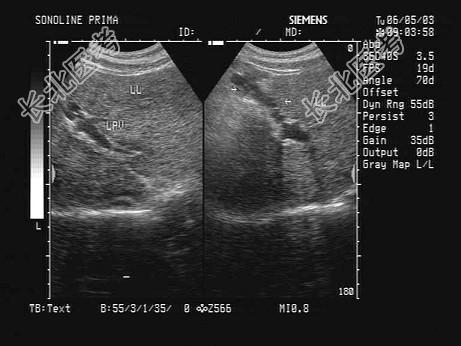

- 单项选择题某患者肝脏声像图表现如图,提示肝脏回声不均匀致密, 肝内可见一管状结构,考虑诊断为   (   )

A、门脉海棉样变性

B、肝淤血

C、脐静脉重开

D、肝内胆管扩张

E、肝血管瘤